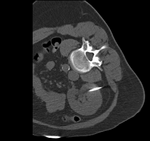

| fixed image/target intra-op CT |

moving image pre-op MRI |

| MR/CT before registration (click to enlarge) | |

| MR/CT after fiducial rigid alignment (click to enlarge) |